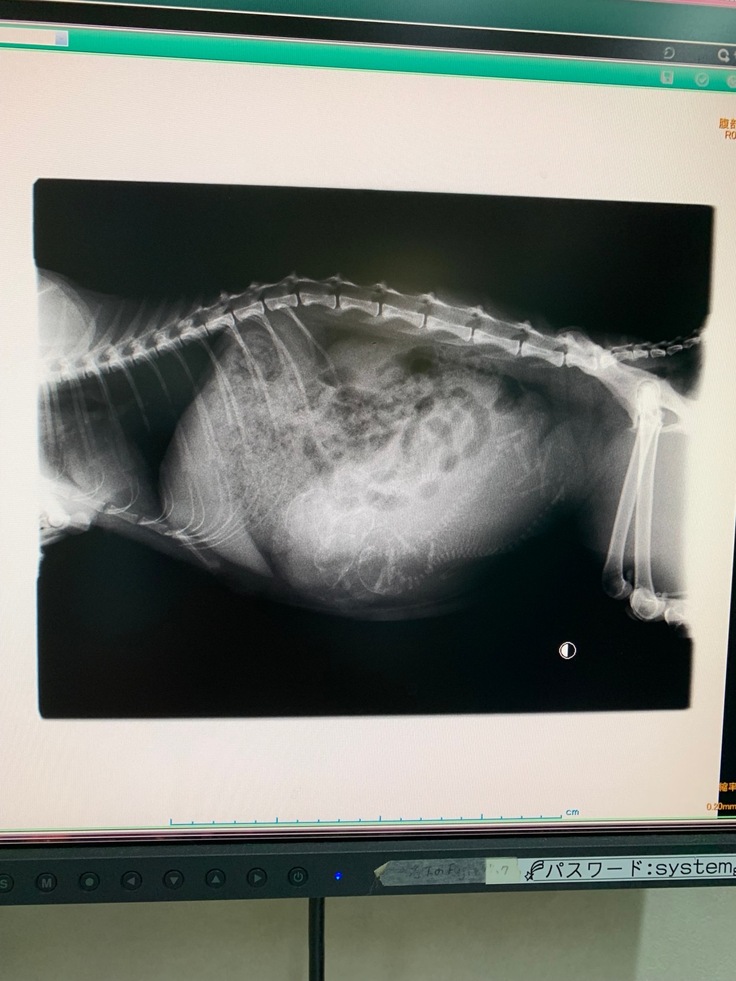

検診のため病院に行きました。

疑いは現実となったのです。

妊娠していました。胎児は4匹いました。

しかも出産はあと2週間後に迫っていました。